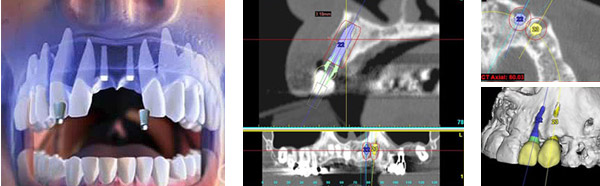

天津市中诺口腔医院(全国连锁·国家二级口腔专科医院)“立得用”种植体系对手术精准度要求更高,采用口腔CBCT技术诊断,从任意角度、任意方位,立体化观察牙槽骨情况,确定科学种植位置,设计出科学种植方案,立种、立用,生物相容性更好,更稳定牢固。

根据顾客牙槽骨密度、高度、宽度,在数字化辅助下自动避开血管和神经,以较短的时间和1微米的创口精度,精准快速种下每一颗种植体,当天做种植牙,当天就能戴牙。

安全预知:种植过程电脑引导,预知效果准确安全。

快速微创:5-10分钟成功种植,微创不翻瓣无缝合。

术前 · 精确诊断 在线预约,享免费检查 >>

• 3三维重建

术中 · 舒适快速 在线咨询,享种牙补贴 >>

• 4微创安全

• 5精准快速